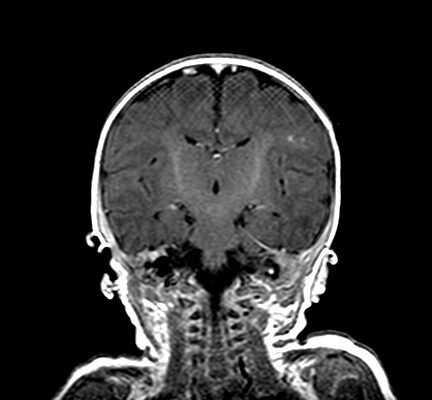

DOI: https://doi.org/10.21980/J8X07MChest radiographs during the initial presentation at seven weeks of life demonstrated right lower lobe (RLL) air space opacity on both PA and lateral views, compatible with pneumonia (referenced by yellow and green arrows, respectively). Repeat chest radiograph performed 12 days after the initial imaging revealed persistent right lower lobe opacity and right hilar fullness, seen as an opacified projection off of the mediastinal border as compared with the prior image, concerning for lymphadenopathy (designated by the aqua arrow). On the third presentation, computed tomography (CT) of the chest with intravenous contrast found persistent right lower lobe consolidation, innumerable 2-3 mm nodules, and surrounding ground glass opacities. This is best visualized as scattered areas of hyperdensity in the lung parenchyma. Axial images confirmed the presence of right hilar as well as subcarinal lymphadenopathy (indicated by white and pink arrows, respectively). Magnetic resonance imaging (MRI) of the brain with IV contrast was performed which showed a punctate focus of enhancement in the left precentral sulcus compatible with a tuberculoma (denoted with red arrow).